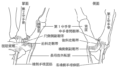

- 外科医は、親指の付け根を切開する前に、手と手首を消毒します。

- 切開部は開創器と呼ばれる器具で開いたままにし、神経と動脈を脇に引っ張ります。

- その後、外科医は僧形骨を除去し、インプラントと置き換えます。

- 傷は縫合して密閉され、柔らかい包帯で覆われます。